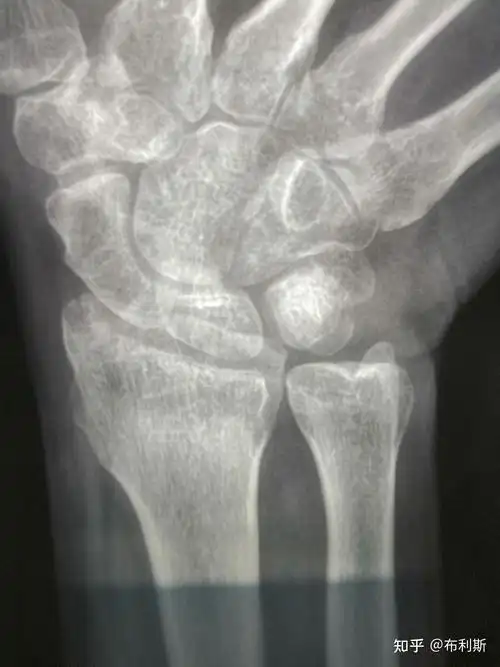

腕舟骨骨折

左手舟状骨骨折

右手腕舟状骨骨折

郑州市骨科医院会诊病例 腕舟骨骨折